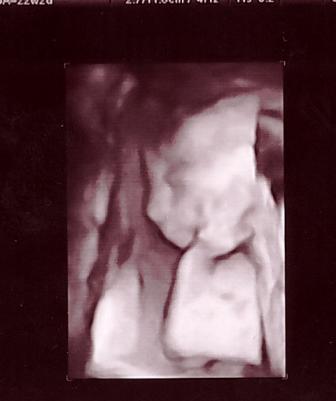

To Viki jeszcze w brzuszku u mamusi.. teraz tez to jej ulubiona poza :)